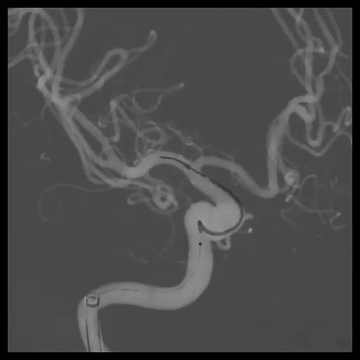

Tubridge Plus Case 5